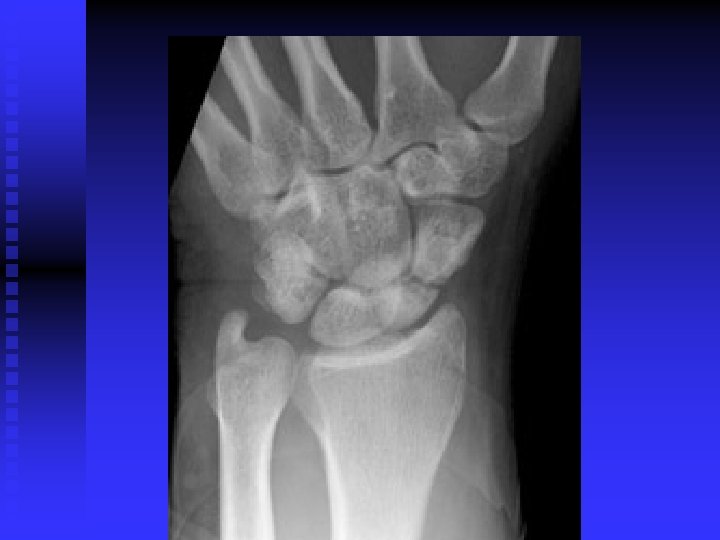

Carpal Tunnel Syndrome n n Median nerve compression within the carpal tunnel is the most common peripheral nerve entrapment syndrome. Any condition that decreases the cross sectional area of the carpal tunnel or increases the volume of its contents may cause the pathology. EX: lunate dislocation; distal radius fracture, sustained flexion or extension postures, fluid retention, synovitis